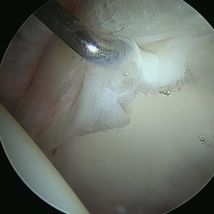

Hip arthroscopy, also referred to as "keyhole" or minimally invasive hip surgery, is typically necessary for hip pain that does not improve with conservative treatment. Small incisions are made only big enough to place a small video camera and specialized instruments into the hip joint, trochanteric space, and/or ischial space to clearly diagnose and treat hip pathology.

- Hip Labral Tear

Click on a hip condition below to see the repair.